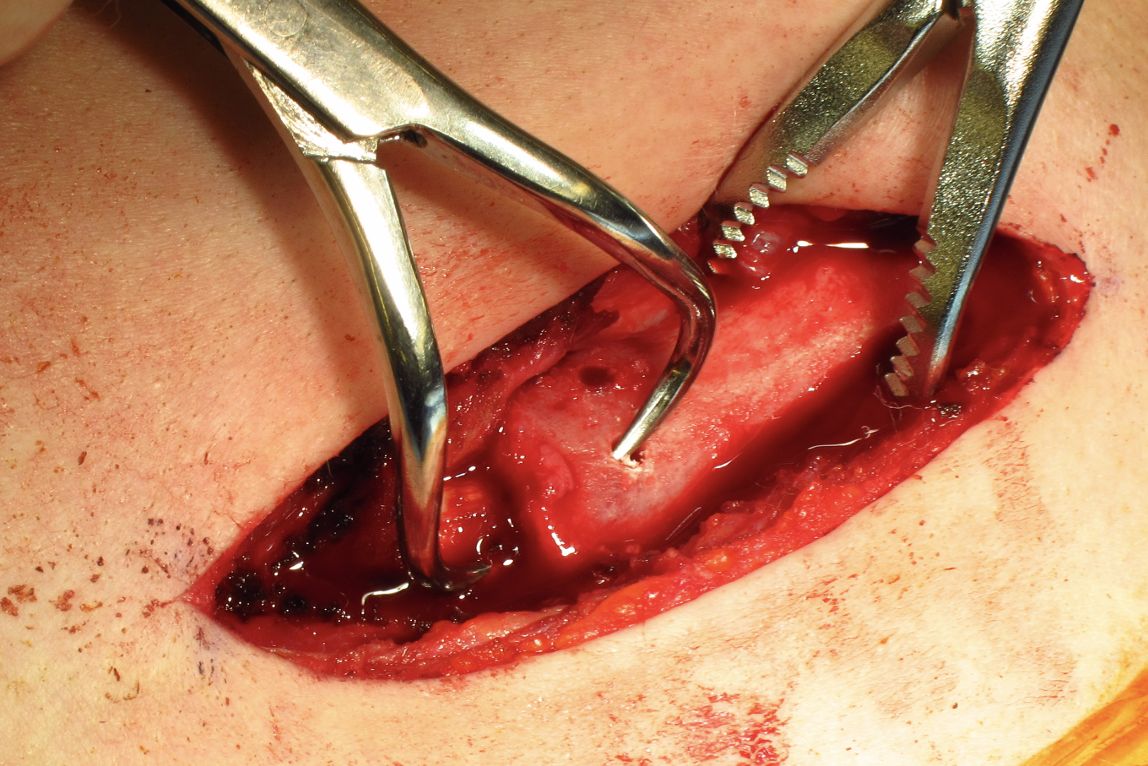

Open reduction of acute posterior sternoclavicular joint dislocation

Drill holes in manubrium and medial clavicle

Figure of 8 suture fixation